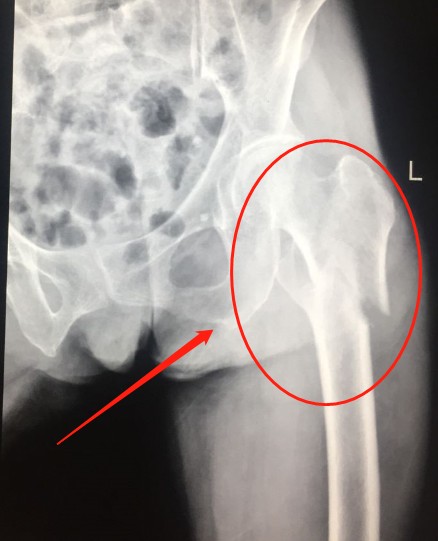

近日,七十多岁的王奶奶(化名)在赶集回家途中被一辆无牌无证电动车迎面撞倒在地,当即感左髋部剧烈疼痛,不能站立行走,

一会儿,医护人员到达现场,并将伤者送到宜宾民心创伤骨科医院抢救,被检查诊断为“左侧股骨粉碎性骨折”。

术前1.png